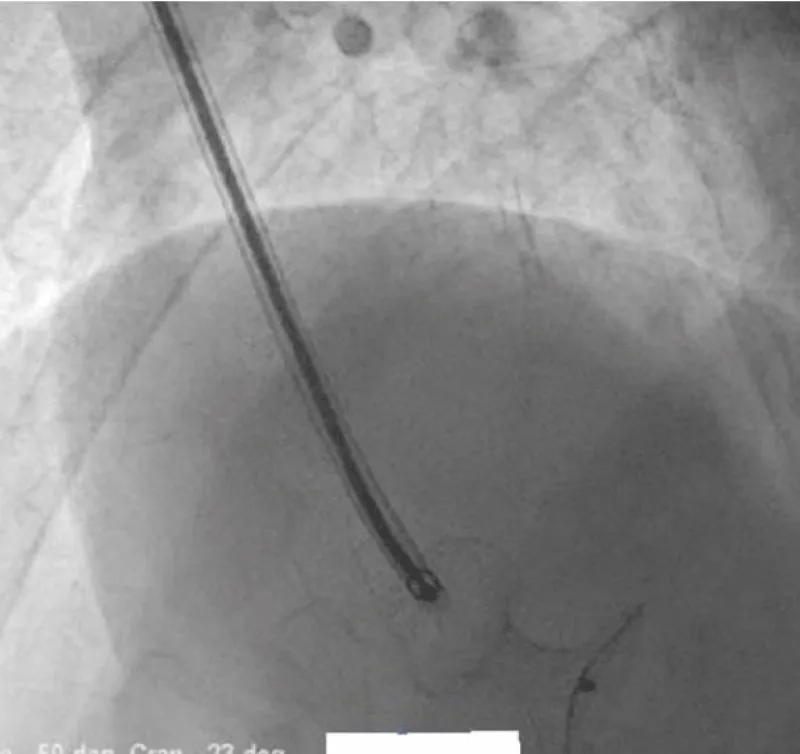

There was no use of transesophageal echocardiography due to the unavailability of a suitable probe. Left Ventricular angiogram was done to determine the exact location of the VSR (Figure 2). Cannulation of the right femoral artery and right internal jugular vein or right femoral vein was performed using the Seldinger technique. A guidewire (03500 Terumo guidewire) was introduced from the femoral artery, through the aorta into the left ventricle, and advanced through the VSR into the right ventricle and pulmonary artery. A second snaring wire was introduced through the vein (Either jugular or femoral) to connect to the guidewire in the pulmonary artery. By retracting the snared wires, the guidewire now forms an arteriovenous (AV) loop. The delivery sheath was advanced from the venous side loop over the guidewire through the VSR into the left ventricle. Correct positioning of the delivery sheath is confirmed in fluoroscopy/TTE. The guidewire is then retracted leaving the delivery sheath in position. After the echocardiographic confirmation occluder device was deployed across VSR using the delivery sheath (Figure 3). Correct positioning of the device and closure was confirmed by transthoracic echocardiography and/or fluoroscopy. If placement is satisfactory, the occluder is released. Post-procedure Left ventricular angiography and transthoracic echocardiography (Figure 4) were done to confirm the position and to rule out the presence of any residual shunt. We did not perform transoesophageal echocardiography for delineation of post-MI VSR, in any of the patients of our series due to the lack of availability of probes. In two cases we did not use any contrast agent (angiography) to delineate VSR because both patients had very high levels of urea and creatinine. Out of 11, in 10 cases, we made use of the femoral-jugular mode of access and created an AV loop. In one case we made a femoral arterio-venous loop. The veno-venous loop though described in literature was not used in this study.

Figure 2: Ventricular angiogram to determine the exact location of the VSR.